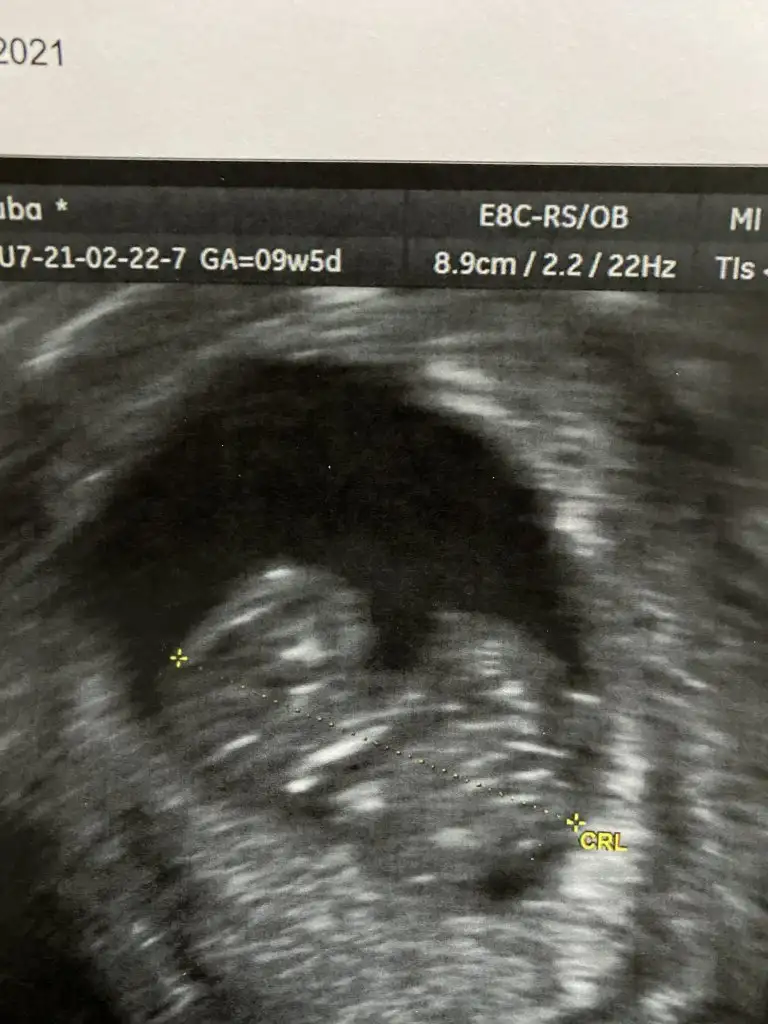

Canım nub a göre cinsel organı oluşturan yapı yatıksa kız deniliyor, senin minnoşun da yatık gibi ama alnı da erkek gibi😊 nub bilmesem erkek derdim.

Merhaba, alnından anlaşılıyor mu acaba benim bebeğimi de yorumlayabilir misiniz? 🙈 9+5 haftalık burda ve yüzünü de görebiliyorum sanki 🤷‍♀️

Kızlarda alnı çıkıntılı olmuyor mu öyle Biliyorum ben. Kafatası uzun çene sivri alnı çıkık. Tipik kız